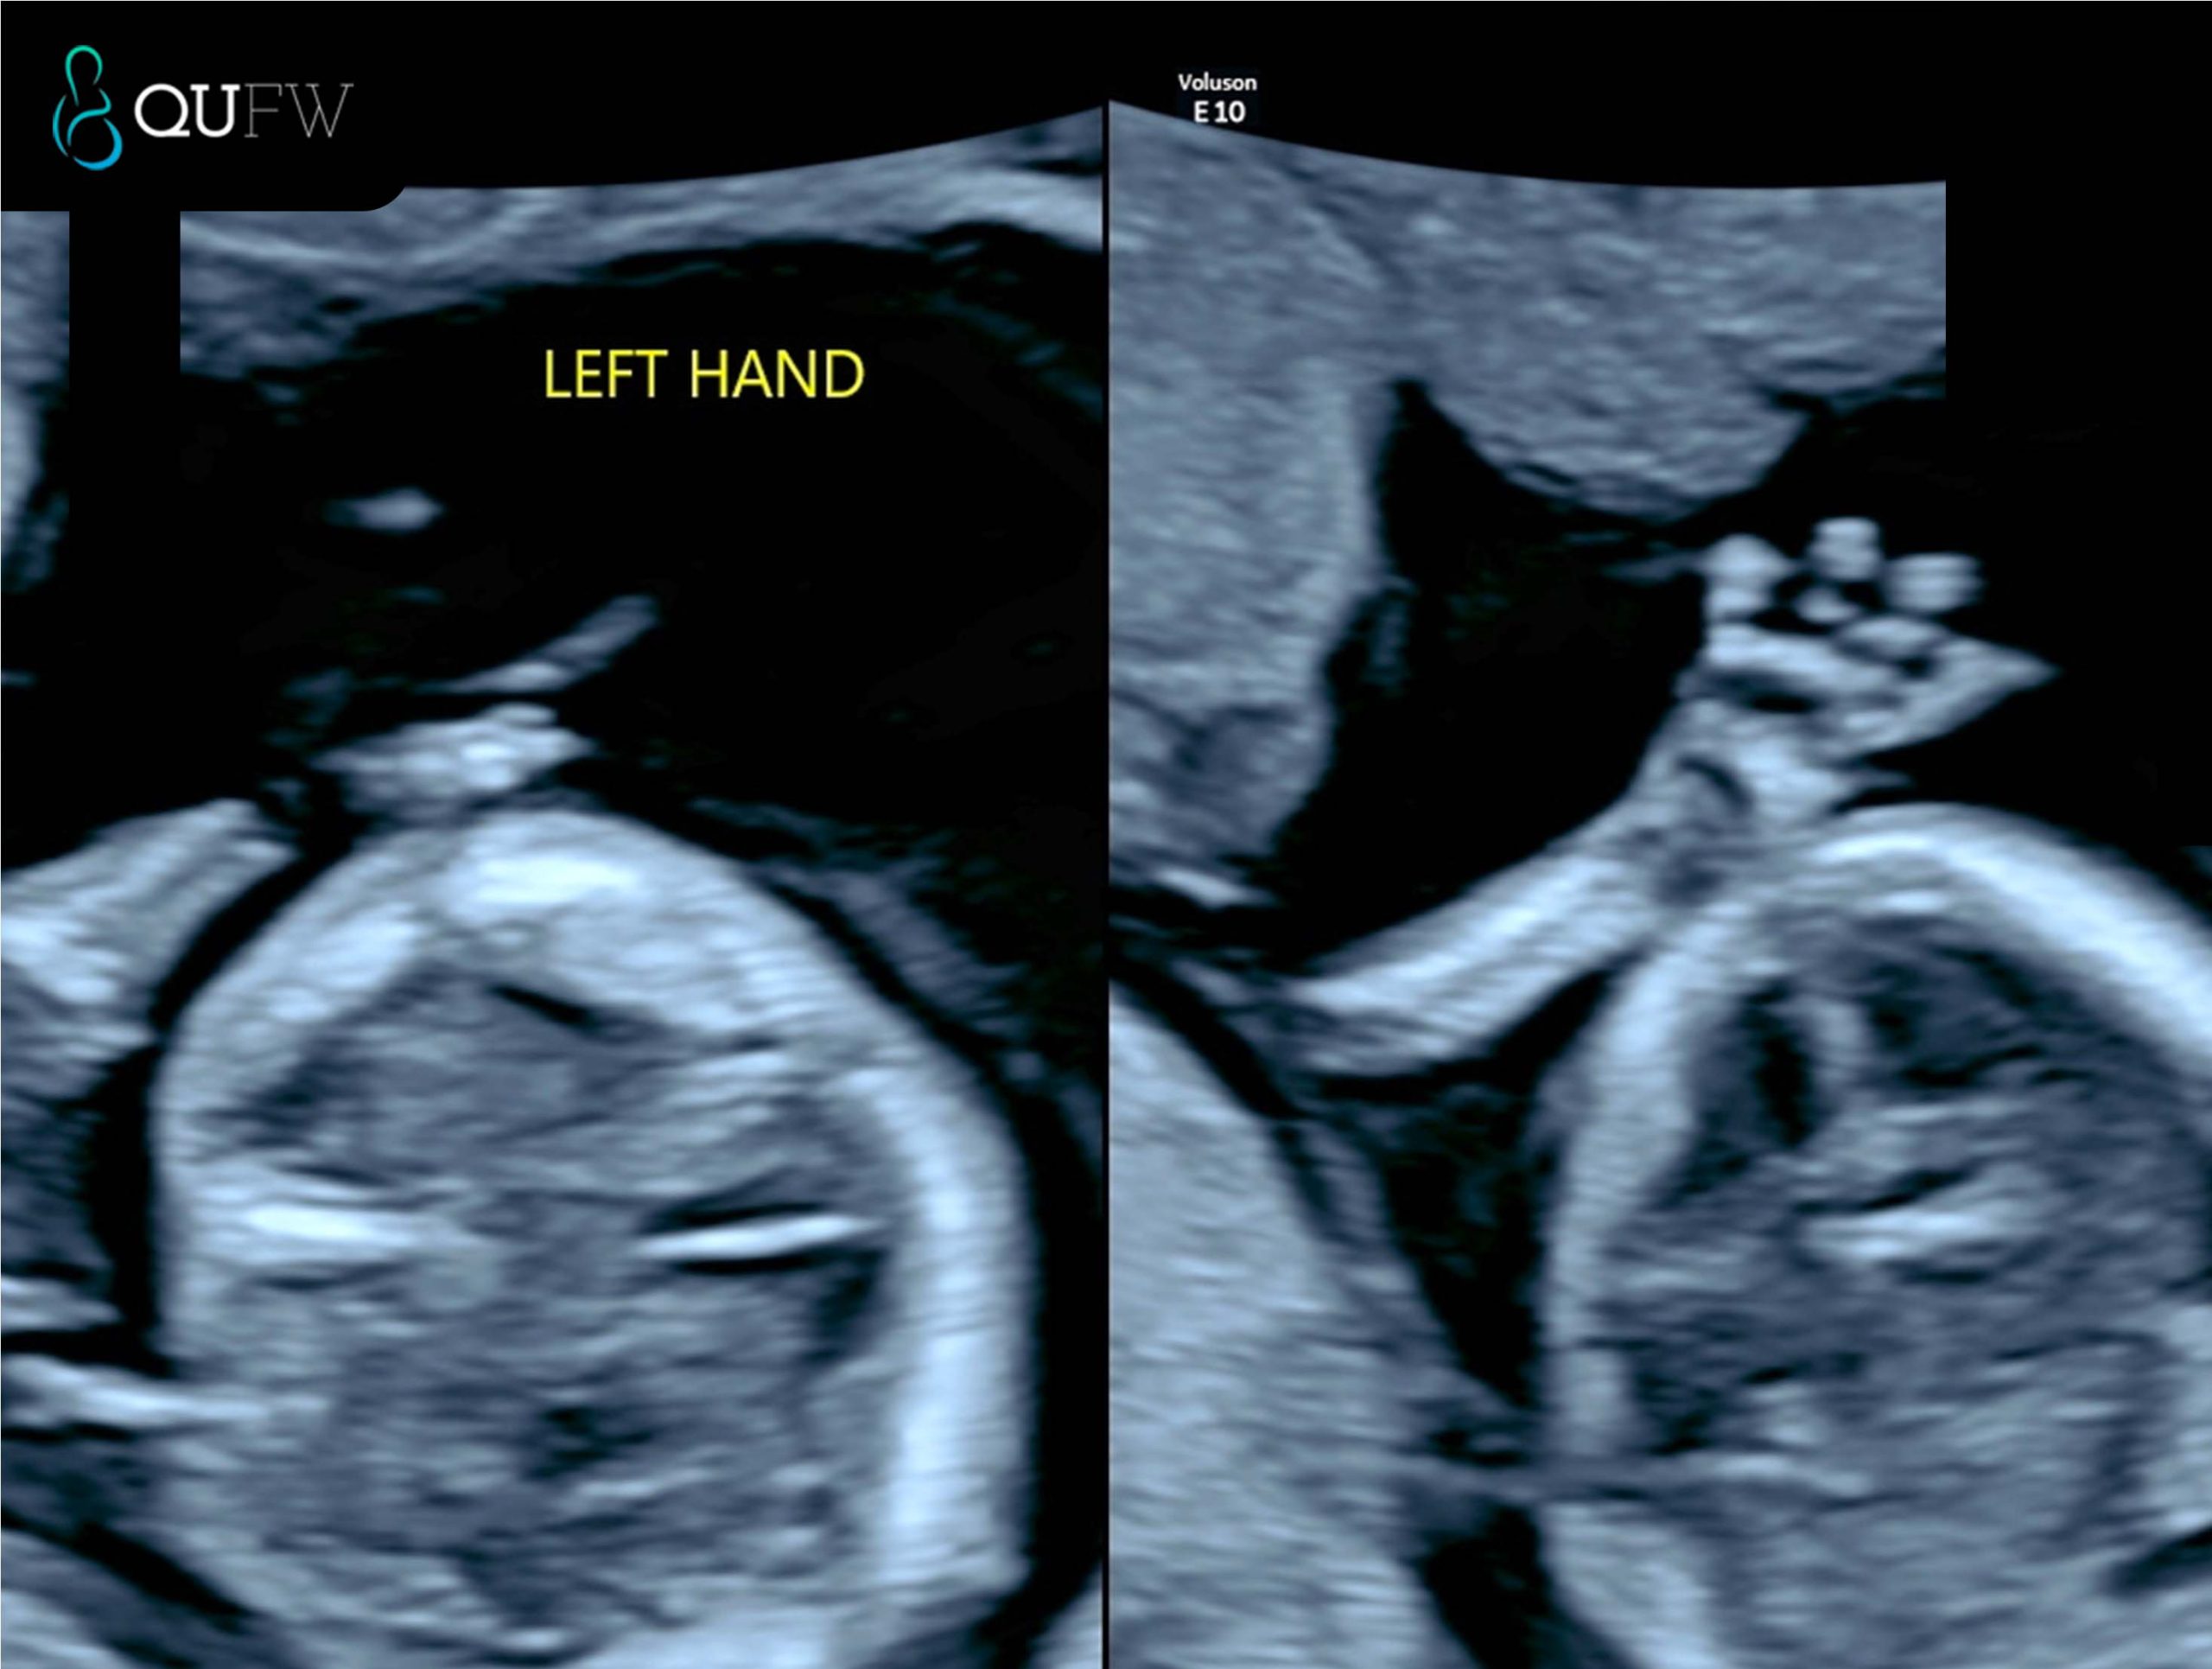

Finally, an early anatomy review is performed, allowing a first assessment of the brain, face, heart, spine, abdomen, abdominal wall, limbs, and other structures. While detailed anatomy scans follow later in pregnancy, this early survey can sometimes detect major abnormalities, giving families and clinicians valuable information sooner.

Early structural assessment of the upper limbs